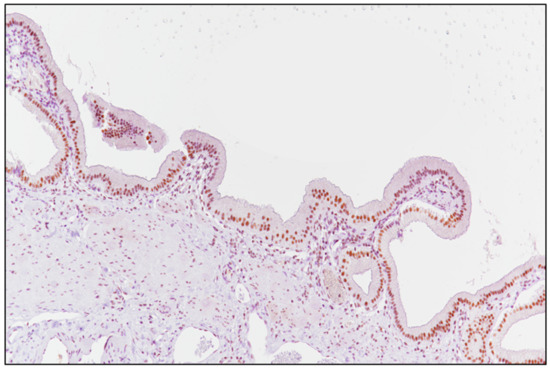

2.2. Laboratory Tests and Evaluation of SRSF1 Immunohistochemistry

3.2. SRSF1 Immunohistochemical Expression and Its Correlation with Prognosis

3.3. SRSF1 Immunoexpression Was Positively Associated with MVD Levels